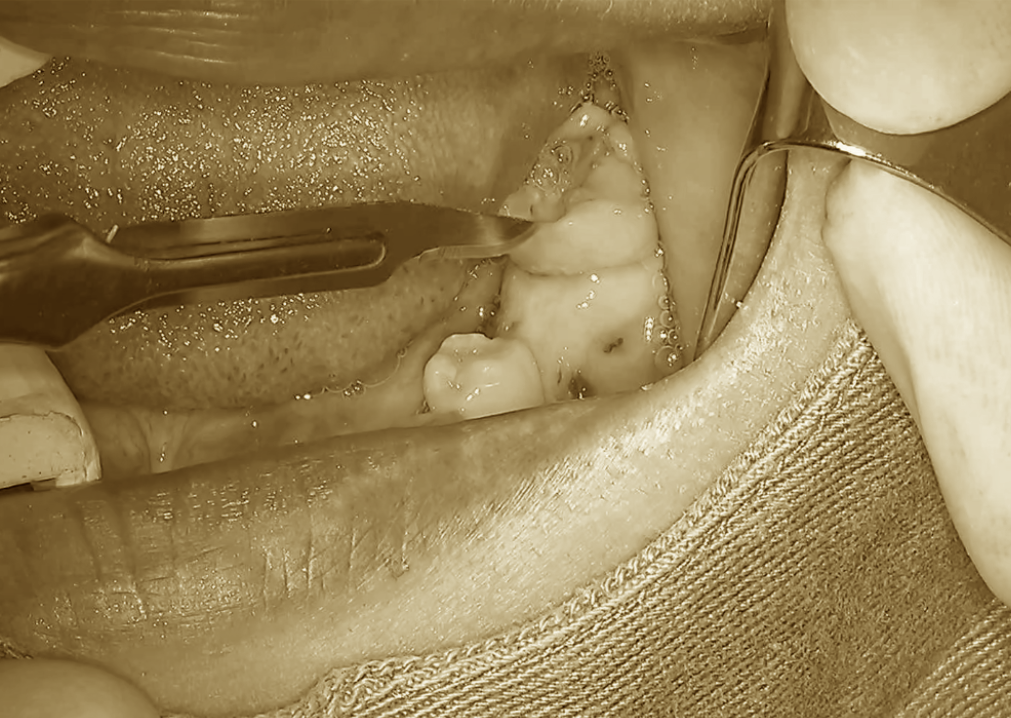

まずは十分に麻酔を行った後、

移植するためのスペース(移植床)を作る工程から始まります。

歯肉を丁寧に切開し、

内部の骨が見える状態まで剥離します。

その後、専用のドリルを使用して

骨に穴を形成していきます。

最初の段階では、

予定している方向と深さが正確かどうかが非常に重要です。

一度ドリルで形成した後、

方向確認用の器具を挿入し、

「狙った位置に正しく形成できているか」

を慎重にチェックします。

問題がなければ、

さらに段階的にドリルを進めていき、

移植歯が適合する形に整えていきます。